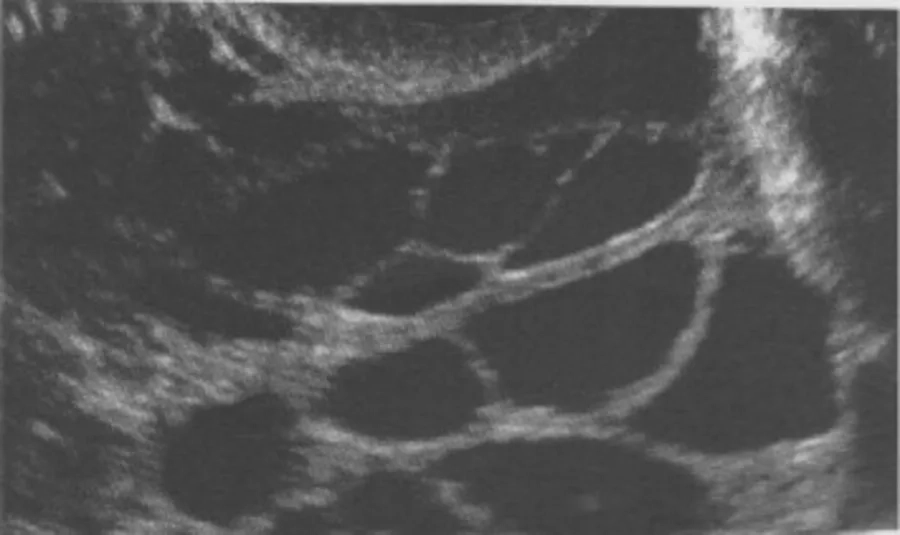

Trước khi xây dựng phác đồ điều trị, bác sĩ cần xác định chính xác bạn có mắc buồng trứng đa nang hay không. Chẩn đoán PCOS hiện nay thường dựa theo tiêu chí Rotterdam 2003, bao gồm: rối loạn rụng trứng, tăng androgen lâm sàng hoặc cận lâm sàng, và hình ảnh buồng trứng đa nang trên siêu âm. Bạn cần có ít nhất 2 trong 3 tiêu chí này và đã loại trừ các nguyên nhân khác.

PCOS là tình trạng mạn tính, đòi hỏi theo dõi và kiểm soát lâu dài. Khám phụ khoa định kỳ, siêu âm buồng trứng và xét nghiệm nội tiết giúp bác sĩ điều chỉnh phác đồ kịp thời, đồng thời phát hiện sớm các rối loạn chuyển hóa đi kèm như kháng insulin hay rối loạn mỡ máu.

- Siêu âm buồng trứng nhằm quan sát số lượng nang noãn và cấu trúc buồng trứng.